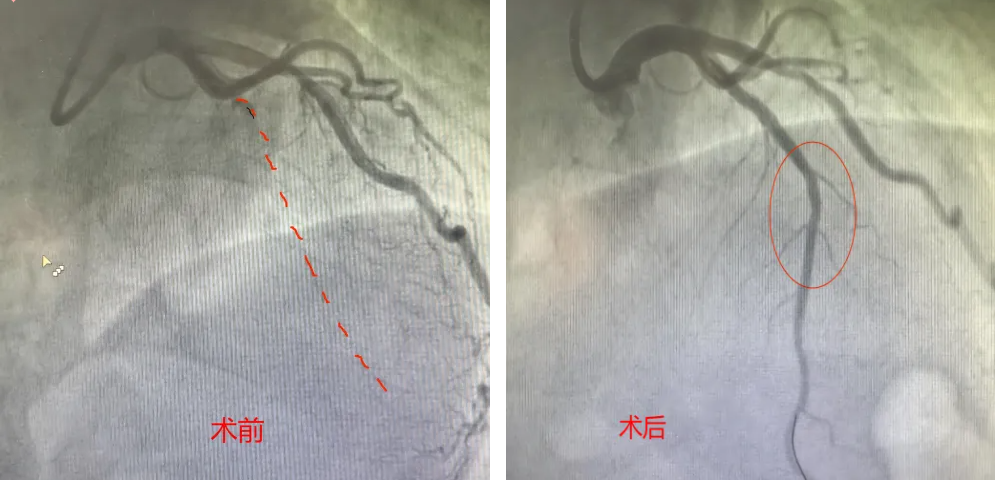

心血管内科团队在张薇教授、焦伟医生密切配合下,成功为患者实施手术,恢复患者心肌正常供血。整个手术过程紧张有序、精准高效,在多学科团队的默契协作下,手术顺利完成。